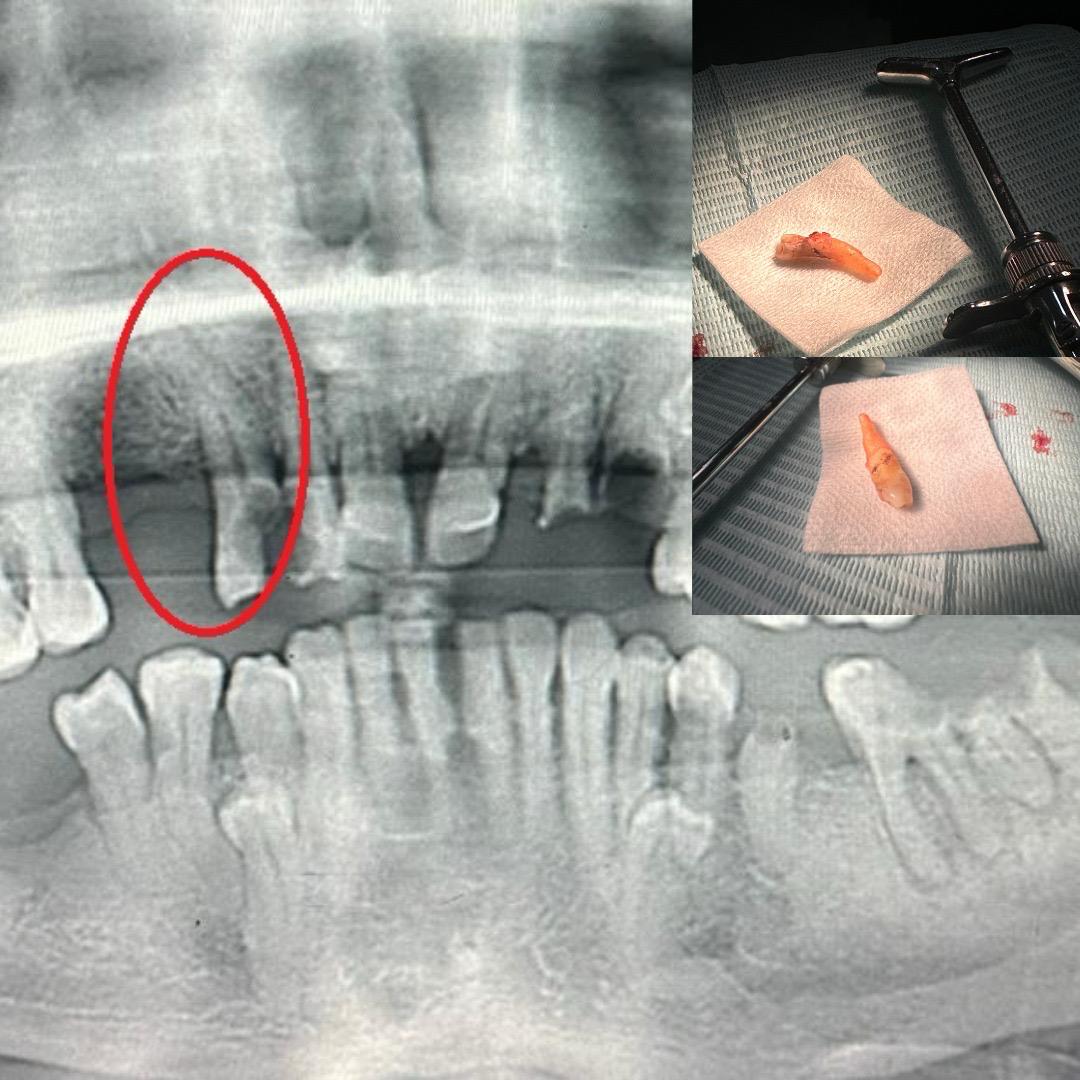

Root canal treatment case Root Canal

Pain Relief & Tooth Saving

Saving a painful tooth that had deep decay and internal infection.

The patient reported severe discomfort while eating and sensitivity that had progressed over time, with a desire to save the natural tooth if possible.

Concern

Deep decay with pain and signs suggesting internal tooth damage.

Treatment

Root canal treatment followed by planned restoration to protect the treated tooth.

Outcome

Tooth preserved, pain addressed, and functional use restored more comfortably.